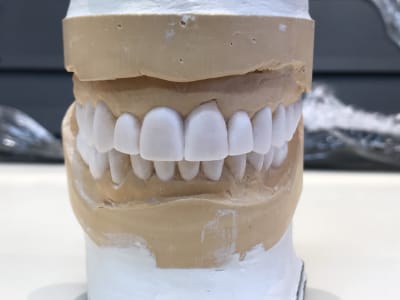

D autant plus que ce n est pas un wax up ça , mais du coloriage blanc .

Pcq le probleme de ce cas est , entre autre , un decentrage lateral du au couple 17/ 47 .

Or il n a pas touché la 47 .

Donc ça ne sert à rien :-)

De + ,Les centrales du haut ,se sont decalées

Or il ne les a meme pas taillees , mais rempli les espaces .

Donc ça ne sert à rien .

A tout les coups il n y a pas eu de centree ( pour cela il aurait fallut limer la 47 ) .

Donc ça ne sert à rien

Le wax up n a d interet que pour proposer 1 nouvelle occlusion , pas pour embellir des faces vestibulaire ,en ayant ouvert la tige incisive .

Clair qu'il est bien moisi ce wax up, après faut voir les instructions, les photos et les divers enregistrements donnés au prothésiste... ici je vois bien un "tu me fais un wax up stp" sur la fiche labo sans rien d'autre, je me trompe ?